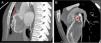

Se presenta el caso de una niña de 11 años con desarrollo pondoestatural normal y asintomática desde el punto de vista cardiovascular, remitida desde su pediatra de zona por auscultación de soplo cardiaco de características funcionales y electrocardiograma patológico con ondas Q en aVL, infradesnivelación del segmento ST en V3-V6 y T negativa en aVL, I y precordiales. Se realizó un ecocardiograma, en el que destaca la salida de la coronaria derecha dilatada en su origen y el origen de la coronaria izquierda en tronco pulmonar con flujo diastólico en tronco pulmonar (fig. 1A,B). El ventrículo izquierdo no estaba dilatado y la función ventricular era normal; se observa un gran desarrollo en las ramas septales y colateral que origina un aspecto del septo interventricular de «corazón en llamas» (fig. 1C). En la tomografía computarizada coronaria se observa el origen anómalo de la coronaria izquierda desde la pared posterior del tronco de la arteria pulmonar con dilatación y tortuosidad de toda la circulación coronaria (fig. 2B), con un calibre de 4-6mm de la coronaria derecha en su origen, y desarrollo de gruesas ramas septales (fig. 2A). Se inició tratamiento con bisoprolol a dosis bajas y se propuso para cirugía de reparación. Se realizó una translocación de coronaria izquierda a aorta y cierre del defecto de la arteria pulmonar con parche de pericardio bovino, con buen resultado y sin complicaciones tras un seguimiento de un año.

A) Salida de la coronaria derecha dilatada en su origen desde el seno de Valsalva derecho (flecha). B) Origen de la coronaria izquierda (flecha) en el tronco pulmonar con flujo diastólico. C) Eje corto del ventrículo izquierdo con gran desarrollo de ramas septales y colateral que origina un aspecto del septo interventricular de «corazón en llamas».

En la mayoría de los casos, en el electrocardiograma se observa un patrón característico: onda Q en las derivaciones I, y avL y alteraciones de la repolarización difusa de V4 a V65. El diagnóstico puede realizarse por ecocardiografía, aunque la técnica de imagen de elección es la tomografía computarizada multicorte. La principal característica morfológica es la detección del origen anómalo y del shunt izquierda-derecha con flujo retrógado desde la coronaria izquierda en la arteria pulmonar. En la forma tardía es característica la dilatación y elongación de la coronaria derecha y las arterias colaterales intercoronarias. La resonancia magnética nuclear puede aportar una valoración funcional de anormalidades en la contractilidad regional, insuficiencia mitral secundaria y áreas de infarto en las secuencias de realce tardío de gadolinio6.